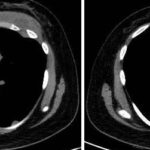

Paciente femenina de 26 años de edad, sin antecedentes patológicos de relevancia, sin dosis de vacuna BCG. Cursa con cuadro clínico de ocho meses de evolución, caracterizado por dolor en región pectoral izquierda intermitente, que se exacerba a la inspiración profunda. En el último mes se palpa masa indurada dolorosa a la palpación a nivel del cuadrante inferior interno de mama izquierda, motivo por el cual se realiza ecografía de partes blandas, donde se observa a nivel retropectoral en íntimo contacto con la parrilla costal imagen hipoecogénica de bordes delimitados, avascular al Doppler color por lo cual se solicita TC de tórax con EV. En ella se observa en topografía del cuarto espacio intercostal, imagen hipodensa con realce periférico tras la administración del contraste que desplaza por efecto de masa el parénquima pulmonar adyacente y se proyecta a la pared torácica anterolateral izquierda; mide 40 mm x 55 mm. Además, se visualiza otra imagen de similares características de base pleural en contacto con el octavo arco costal posterior izquierdo que mide 6 mm x 11 mm.

Cuatro meses posteriores a la PAAF la paciente refiere persistencia de dolor y aumento de tamaño de la masa asociado a eritema en región mamaria, por lo cual se realiza TC de tórax con contraste EV donde se observa imagen hipodensa ya conocida, con realce periférico tras la administración de contraste, con aumento de tamaño y bordes lobulados.

La tomografía computarizada proporciona información más detallada sobre el compromiso extrapulmonar, revelando ganglios linfáticos mediastinales aumentados o nódulos subpleurales que sugieren focos de infección activa.